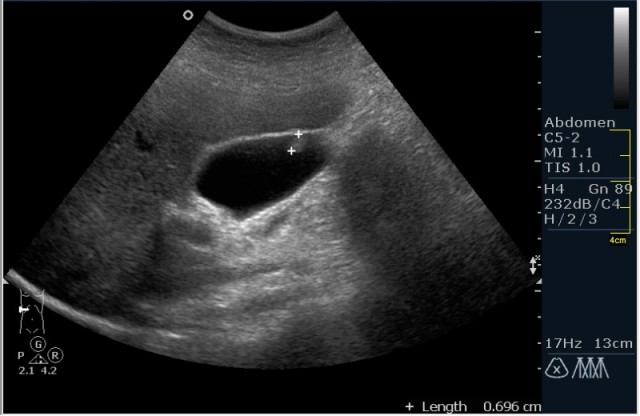

- УЗИ;

Первый метод позволяет определить как множественные, так и единичные новообразования на слизистой органа. Необходимо отметить, что в некоторых случаях во время проведения УЗИ органа за холестериновые полипы принимают сгустки желчи.

В остальных случаях специалист наблюдает за течением заболевания на протяжении некоторого времени. Строение полипов и их количество определяют частоту наблюдений. Если новообразование имеет ножку, то УЗИ органа можно проводить 1 раз в течение полугода. Если же ножек у наростов нет, то наблюдать их необходимо гораздо чаще. Такие новообразования могут перерасти в злокачественную карциному.